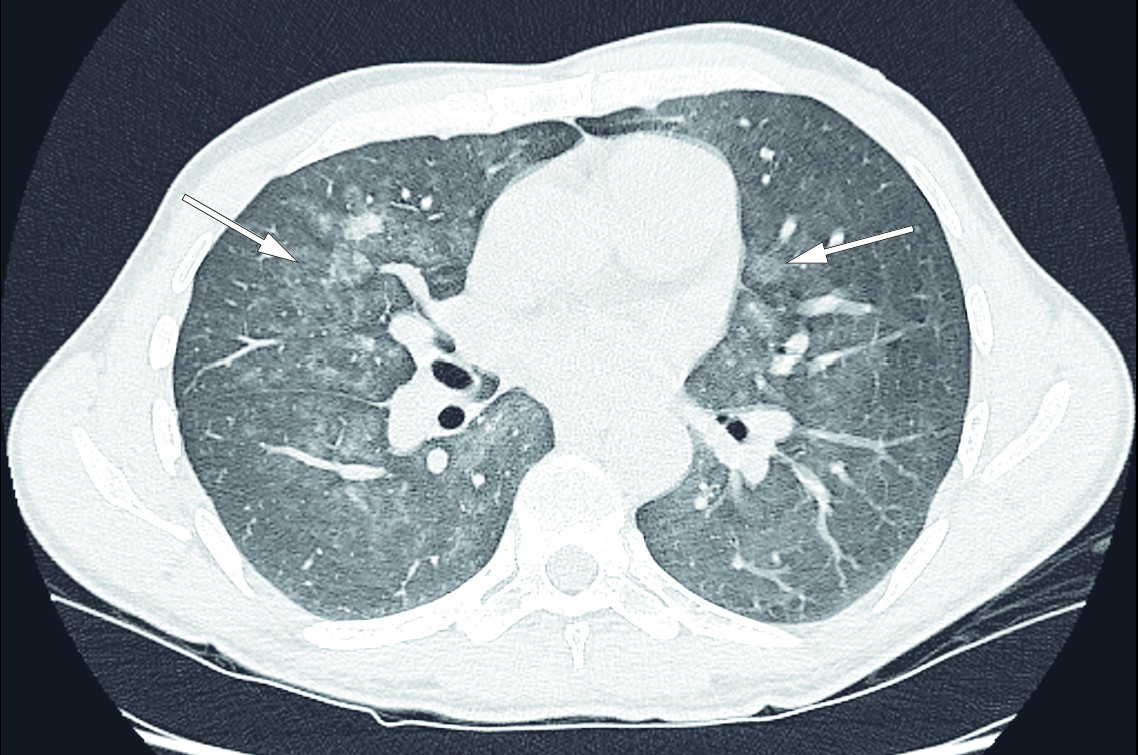

A new CT thorax performed four weeks after the last scan showed that bilateral, patchy ground glass opacities had appeared in the mid fields of the lungs (Figure 2). In addition to the differential diagnoses described on PET-CT, interstitial lung disease and bleeding due to vasculitis were proposed as differential diagnoses.